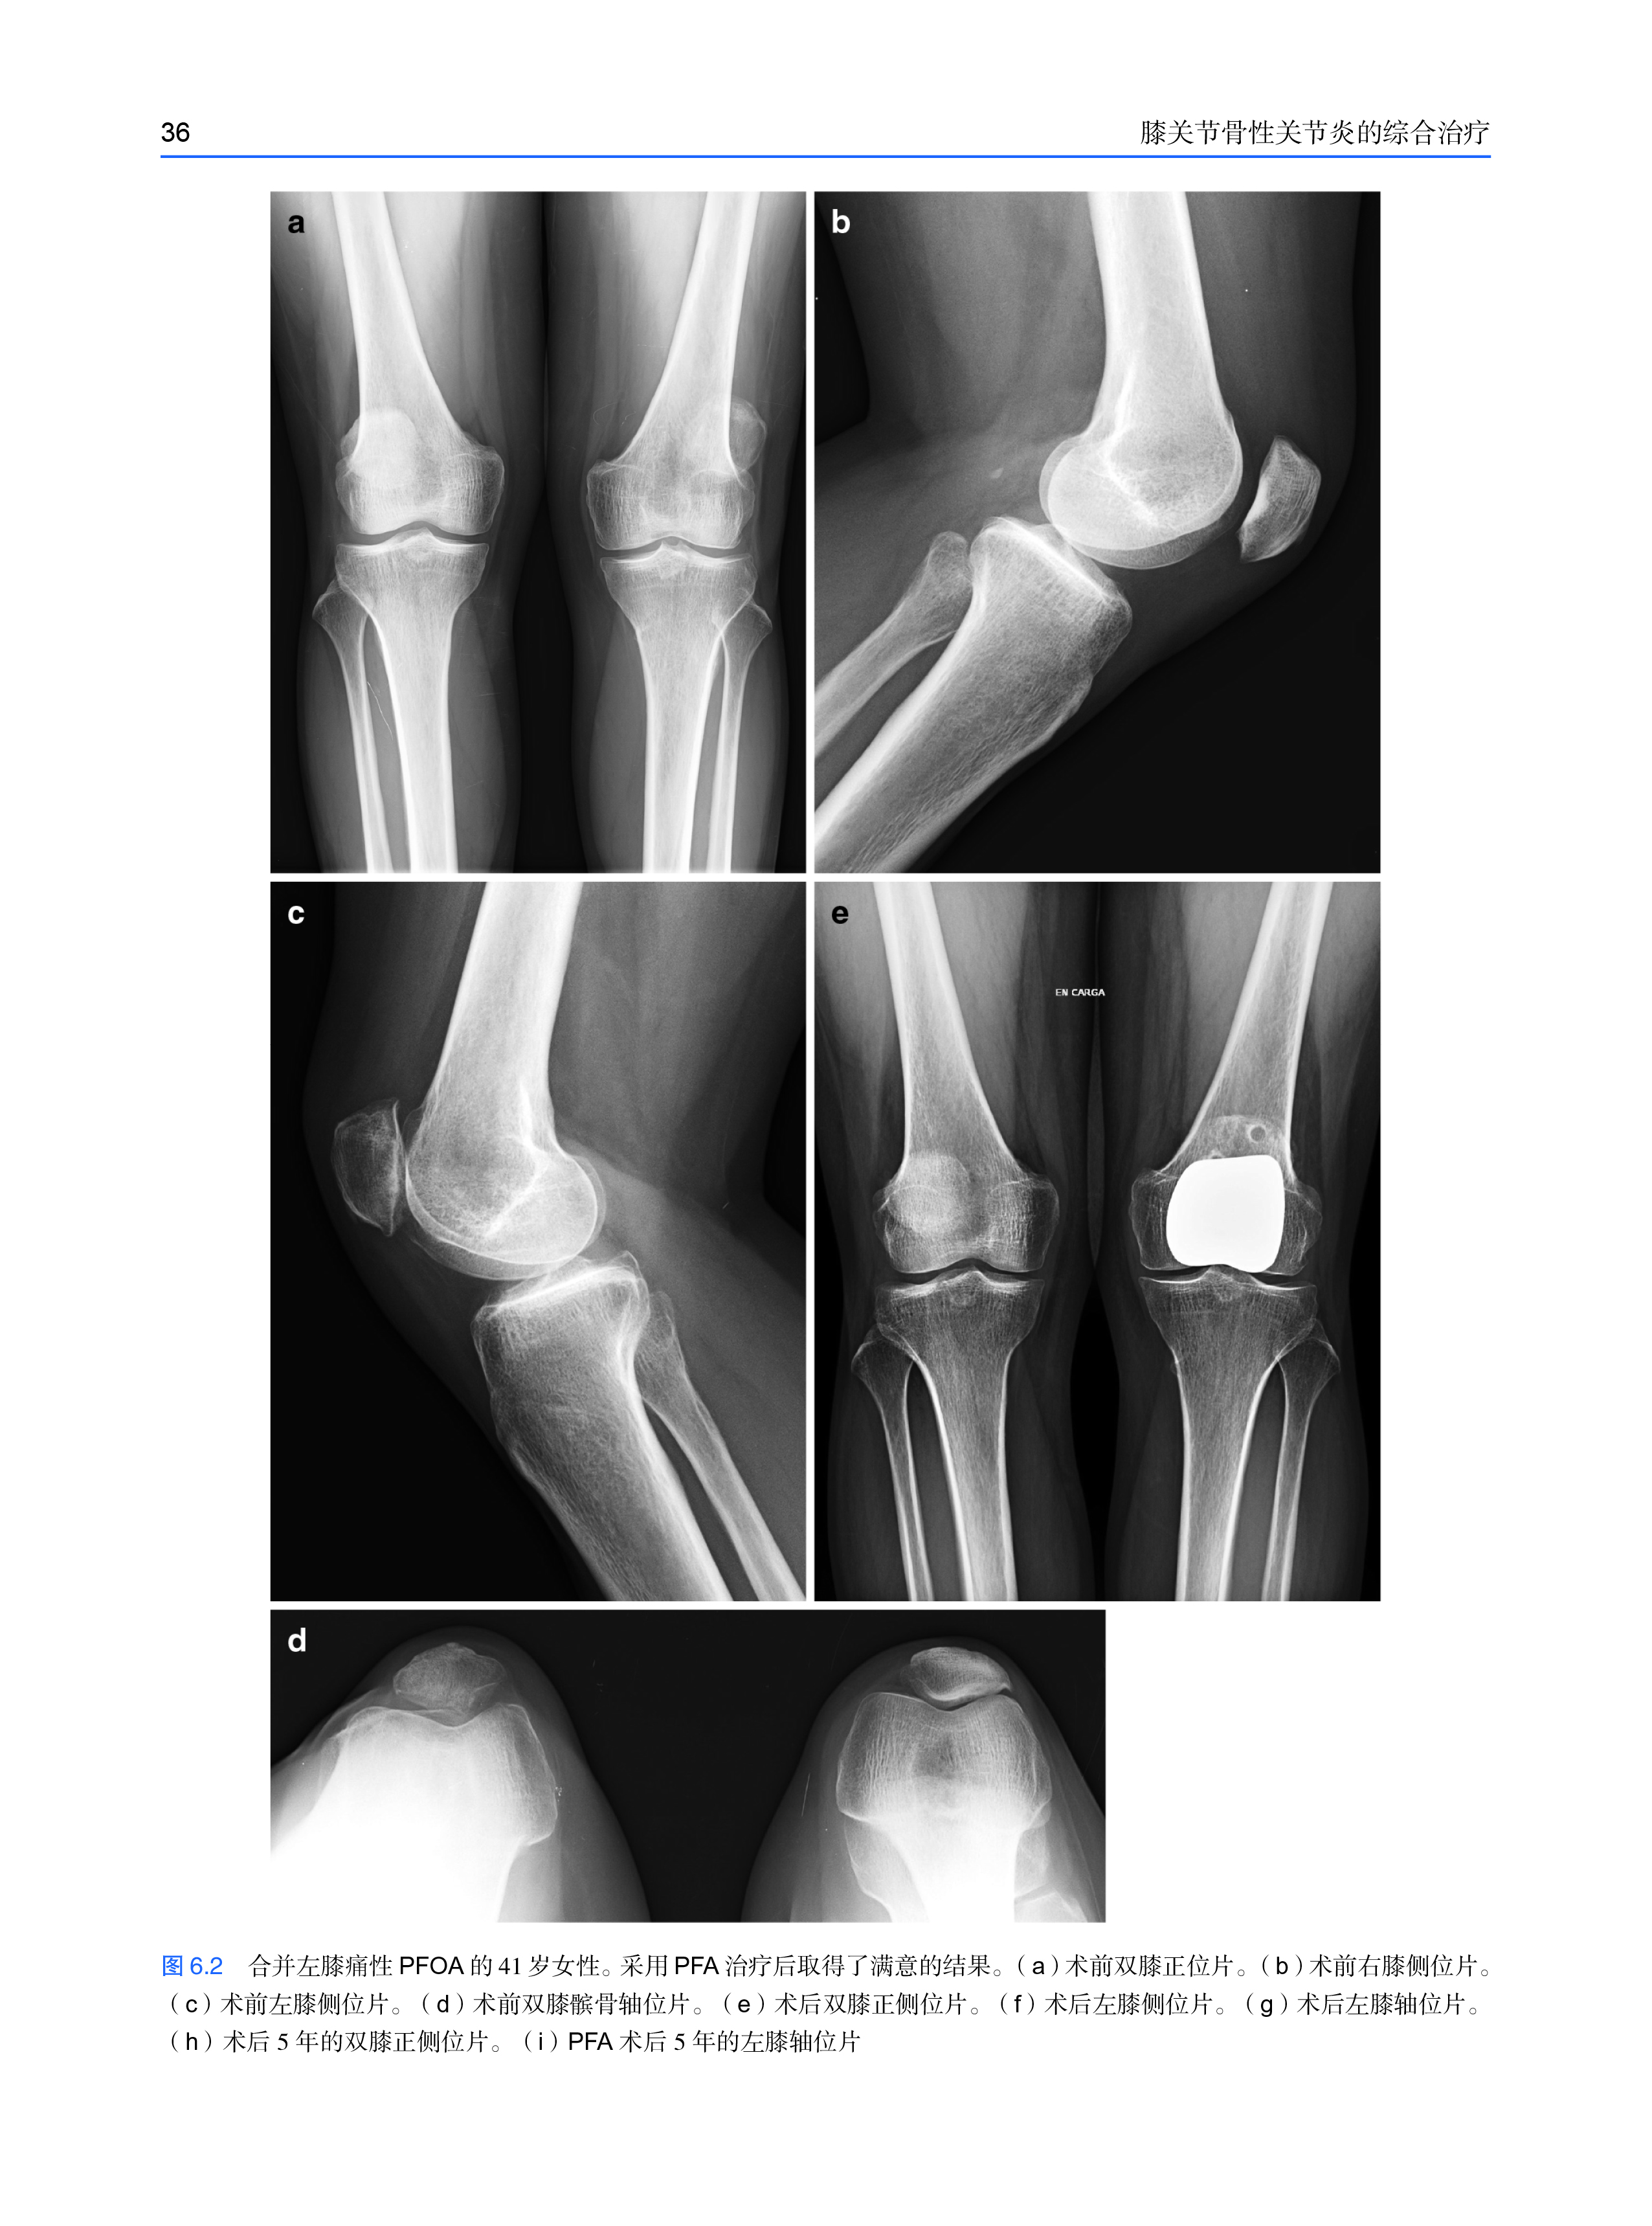

本书不仅系统、全面地阐述了膝关节骨性关节炎的综合治疗方法,还涵盖了膝关节骨性关节炎的初始治疗、物理和康复治疗、保守和手术治疗。通过这些治疗等多个方面学习,对膝关节骨性关节炎充分理解有助于我们对手术及治疗更全面的评估。此外,本书还介绍了单间室、三间室、全膝关节置换术、术中动脉损伤、术后感染、术后僵硬、术后翻修、假体周围骨折等手术经验及技巧。通过学习书中知识和技巧,可以对膝关节骨性关节炎的综合治疗原理和方法有了更深的认识,结合对既往相关临床工作的反思,从中受益匪浅。